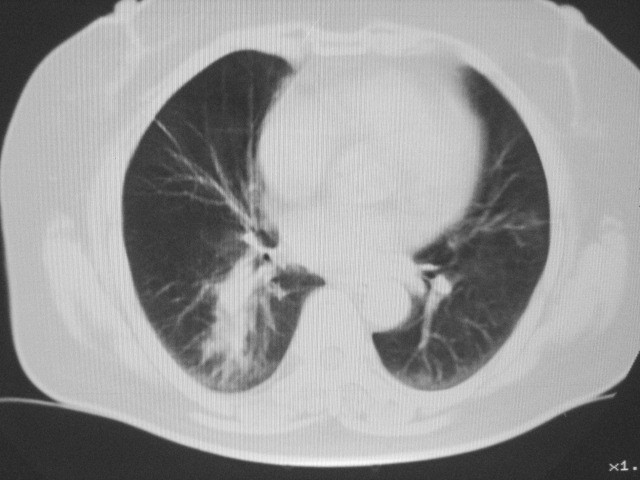

以下是引用清清楚楚在2007-8-28 7:13:00的发言:[br]右肺下叶可见斑片状高密度影,边缘模糊;右肺中叶内侧段及左肺舌段亦可见小斑片状模糊影。[br]考虑双肺感染,建议抗炎治疗后复查。

以下是引用天南地北在2007-8-27 23:49:00的发言:[br]右肺下叶可见斑片状高密度影,边缘模糊;右肺中叶内侧段及左肺舌段亦可见小斑片状模糊影。[br]考虑双肺感染,建议积极抗炎治疗后复查。

以下是引用天南地北在2007-8-27 23:49:00的发言:[br]右肺下叶可见斑片状高密度影,边缘模糊;右肺中叶内侧段及左肺舌段亦可见小斑片状模糊影。[br]考虑双肺感染,建议抗炎治疗后复查。

以下是引用难听在2007-8-28 13:17:00的发言:[br]右肺下叶背段支气管狭窄,是否可以考虑新生物伴阻塞性肺炎.请大家帮帮忙,这个病人是卫生局长的丈母娘.惹不起啊.